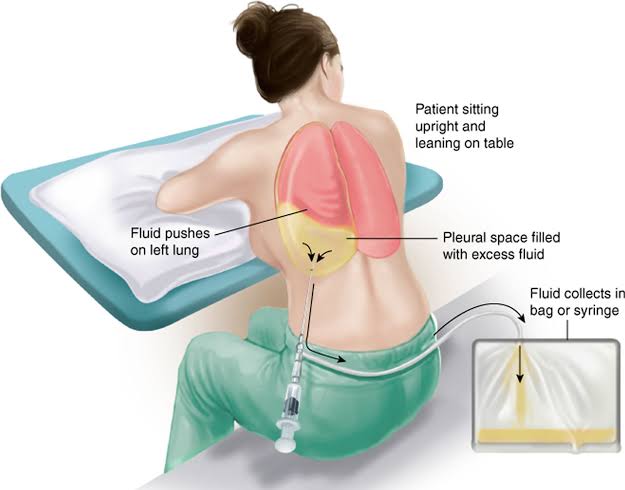

Thoracocentesis (થોરાકોસેન્ટેસીસ):

- થોરાકોસેન્ટેસીસ એ એક ડાયગ્નોસ્ટિક અને થેરાપ્યુટિક પ્રોસિઝર છે.

- જેમાં લંગ અને ચેસ્ટ વોલની વચ્ચે આવેલ પ્લુરલ સ્પેસમાંથી નીડલ અથવા પ્લાસ્ટિક કેથેટરની મદદથી ફ્લૂઇડ એસ્પીરેટ કરવામાં આવે છે અને આ પ્લુરલ ફલુઇડનું એનાલાયસીસ કરવામાં આવે છે.

- નોર્મલી પ્લુરલ સ્પેસમાં થોડી માત્રામાં પ્લુરલ ફ્લૂઇડ આવેલું હોય છે. જો વધારે માત્રામાં આવેલ હોય તો તે કોઈ ડીઝીસ કન્ડિશન ઇન્ડિકેટ કરે છે.

- આ પ્લુરલ ફ્લુઇડને ગ્રામ સ્ટેઇન કલ્ચર અને સેન્સિટીવિટી, એસિડ ફાસ્ટ સેન્સિટીવિટી અને કલ્ચર, ડિફરન્ટ સેલ કાઉન્ટ, સાઇટોલોજી PH, સ્પેસિફિક ગ્રેવિટી અને ટોટલ પ્રોટીન માટે સ્ટડી કરવામાં આવે છે.

- આ પ્રોસિજર અલ્ટ્રાસાઉન્ડના ગાઇડન્સ હેઠળ કરવામાં આવે છે.